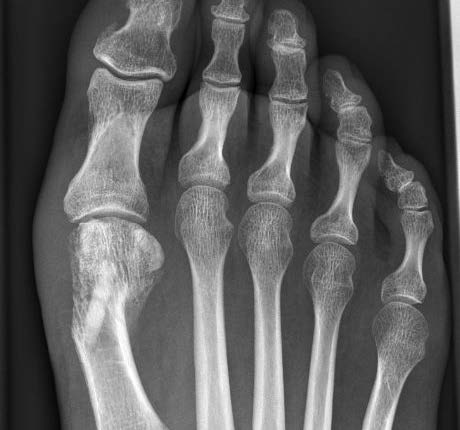

8 Wochen postoperativ

Guter Durchbau der Osteotomie und guter Halt des Transplantats.